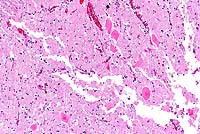

- Case 18-3. Lung. There is diffuse bronchiolar epithelial

necrosis with scattered eosinophilic intranuclear inclusions

(arrowhead), and several syncytial cells in various stages of

degeneration. The bronchial lumen is filled with cell debris

and the pulmonary interstitium is expanded by edema, a mixed

cellular infiltrate, and cellular debris.

- AFIP Diagnosis: Lung: Pneumonia, broncho-interstitial,

necrotizing, acute, diffuse, severe, with syncytial cells, eosinophilic

intranuclear inclusion bodies, edema, hemorrhage, and fibrin,

breed unspecified, equine, etiology consistent with equine herpesvirus

type I.